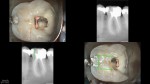

This patient was in yesterday for a different tooth, and we can see the pulp horn to the mesial along with drawings showing traditional SLA and how much tooth structure might have been left.

This was also a deep finish line case where my advice (to a new clinician in town) to leave the distal finish line on amalgam was not heeded. Ferrule only counts if the crown fits. Here…it doesn't seem to have mattered although I don't think anyone would be happy about that process outcome. I don't think it should be revised either, as there isn't any evidence that even the process outcome would be improved by such a revision.